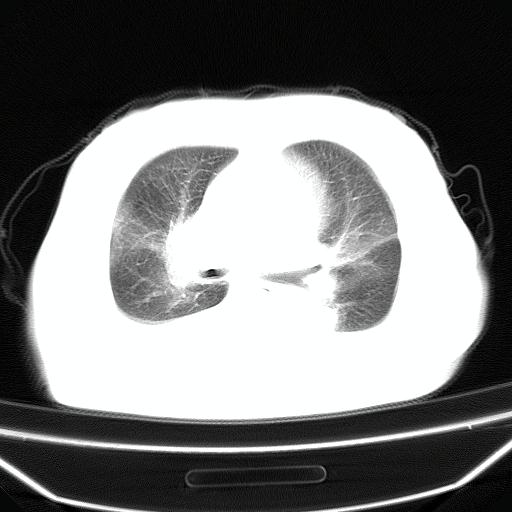

以下是引用liuyue在2008-4-19 22:25:00的发言:[br]先考虑:1.心衰伴肺水肿、双侧胸腔积液、叶间积液、双下肺不完全性肺不张; [br] 2.冠状动脉粥样硬化。

以下是引用jiangjing在2008-4-20 10:43:00的发言:[br]结合病史支持 冠心病[冠状动脉钙化],心功能不全,肺淤血、肺水肿,双侧胸腔与斜裂积液